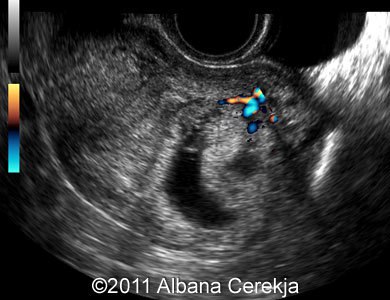

الصور الشعاعية للحمل خارج الرحم بقلم الدكتور صفاء نوري سلمان

يُعد الحمل خارج الرحم (Ectopic Pregnancy) حالة طبية خطيرة تحدث عندما تنغرس البويضة المخصبة خارج الرحم، وغالبًا في قناة فالوب. التشخيص المبكر باستخدام الصور الشعاعية ضروري لتجنب المضاعفات الخطيرة.<br />2. دور الصور الشعاعية في التشخيص<br />- الأشعة فوق الصوتية (Ultrasound):<br /> - الوسيلة الأكثر استخدامًا في تشخيص الحمل خارج الرحم.<br /> - يتم استخدام التصوير عبر المهبل للحصول على صور دقيقة.<br /> - العلامات: غياب كيس الحمل في الرحم مع وجود كتلة في قناة فالوب.<br />- التصوير بالأشعة السينية (X-ray):<br /> - يُستخدم في حالات نادرة إذا اشتبه بوجود نزيف داخلي.<br />- التصوير بالرنين المغناطيسي (MRI):<br /> - يُستخدم لتأكيد التشخيص في الحالات المعقدة.<br />3. الأعراض المصاحبة التي تدعم الفحص<br />- ألم شديد في الحوض أو البطن.<br />- نزيف مهبلي غير طبيعي.<br />- دوخة أو إغماء نتيجة انخفاض ضغط الدم بسبب النزيف الداخلي.<br />4. أهمية التشخيص المبكر<br />يساعد في تقليل المخاطر المرتبطة بالنزيف الداخلي. يُمكّن الأطباء من اتخاذ الإجراءات المناسبة، مثل العلاج الدوائي أو الجراحي.<br />5. طرق العلاج بناءً على الصور الشعاعية<br />- العلاج الدوائي:<br /> - ميثوتريكسيت يُستخدم لإنهاء الحمل غير الطبيعي إذا تم التشخيص مبكرًا.<br />- الجراحة:<br /> - إجراء تنظير البطن لإزالة الحمل خارج الرحم.<br /> - يتم اللجوء إليها إذا تسبب الحمل في تمزق قناة فالوب أو حدوث نزيف داخلي.<br />6. الختام<br />تُعد الصور الشعاعية أداة أساسية لتشخيص الحمل خارج الرحم والتعامل معه بسرعة لتجنب <br />